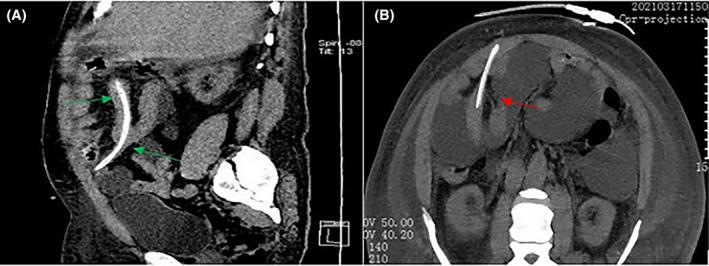

Delayed intestinal perforation has various manifestations. For peritonitis with delayed treatment and multi-bacterial peritonitis, we should be alert to the occurrence of this rare complication. Abdominal CT examination and imaging results judgment based on clinical conditions are particularly important for diagnosis. Delayed intestinal perforation of peritoneal dialysis catheter is a rare but serious complication. We reported a 49-year-old patient who had been hospitalized twice within 3 months due to poor drainage of the peritoneal dialysis catheter. During the first hospitalization, peritoneal dialysis-related peritonitis was diagnosed, and a variety of bacterial infections were cultivated. However, at that time, the actual peritoneal dialysis catheter-related intestinal perforation was missed, and he was discharged after anti-infection treatment until a clinical cure was met. After more than 2 months of normal peritoneal dialysis after returning home, the patient again had poor drainage of the peritoneal dialysis catheter, accompanied by the outflow of yellowish-brown sediment. It was found that the peritoneal dialysis catheter had evidence of intestinal perforation. After the removal of the catheter and intestinal repair, he recovered and was discharged from the hospital and received long-term hemodialysis treatment. In the case of delayed intestinal perforation, peritoneal dialysis was maintained normally for more than 2 months, which was an unprecedented situation in previous case reports. In addition, we should be alert to the occurrence of this rare complication, especially when we find the occurrence of polybacterial Peritonitis. Abdominal CT examination and imaging results judgment based on clinical conditions are particularly important for diagnosis.

迟发性肠穿孔有多种表现。对于治疗延迟的腹膜炎和多菌性腹膜炎,我们应警惕这种罕见并发症的发生。腹部CT检查以及基于临床情况的影像学结果判断对诊断尤为重要。腹膜透析导管相关的迟发性肠穿孔是一种罕见但严重的并发症。我们报告了一名49岁患者,其因腹膜透析导管引流不畅在3个月内两次住院。第一次住院期间,诊断为腹膜透析相关性腹膜炎,培养出多种细菌感染。然而,当时实际存在的腹膜透析导管相关肠穿孔被漏诊,经抗感染治疗直至临床治愈后出院。回家正常腹膜透析2个多月后,患者再次出现腹膜透析导管引流不畅,伴有黄褐色浑浊物流出。发现腹膜透析导管存在肠穿孔迹象。拔除导管并进行肠修复后,患者康复出院,接受长期血液透析治疗。在迟发性肠穿孔的情况下,腹膜透析正常维持了2个多月,这在以往病例报道中是前所未有的情况。此外,我们应警惕这种罕见并发症的发生,尤其是当发现多菌性腹膜炎发生时。腹部CT检查以及基于临床情况的影像学结果判断对诊断尤为重要。